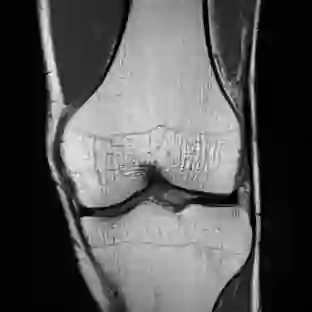

Limited by imaging systems, the reconstruction of Magnetic Resonance Imaging (MRI) images from partial measurement is essential to medical imaging research. Benefiting from the diverse and complementary information of multi-contrast MR images in different imaging modalities, multi-contrast Super-Resolution (SR) reconstruction is promising to yield SR images with higher quality. In the medical scenario, to fully visualize the lesion, radiologists are accustomed to zooming the MR images at arbitrary scales rather than using a fixed scale, as used by most MRI SR methods. In addition, existing multi-contrast MRI SR methods often require a fixed resolution for the reference image, which makes acquiring reference images difficult and imposes limitations on arbitrary scale SR tasks. To address these issues, we proposed an implicit neural representations based dual-arbitrary multi-contrast MRI super-resolution method, called Dual-ArbNet. First, we decouple the resolution of the target and reference images by a feature encoder, enabling the network to input target and reference images at arbitrary scales. Then, an implicit fusion decoder fuses the multi-contrast features and uses an Implicit Decoding Function~(IDF) to obtain the final MRI SR results. Furthermore, we introduce a curriculum learning strategy to train our network, which improves the generalization and performance of our Dual-ArbNet. Extensive experiments in two public MRI datasets demonstrate that our method outperforms state-of-the-art approaches under different scale factors and has great potential in clinical practice.